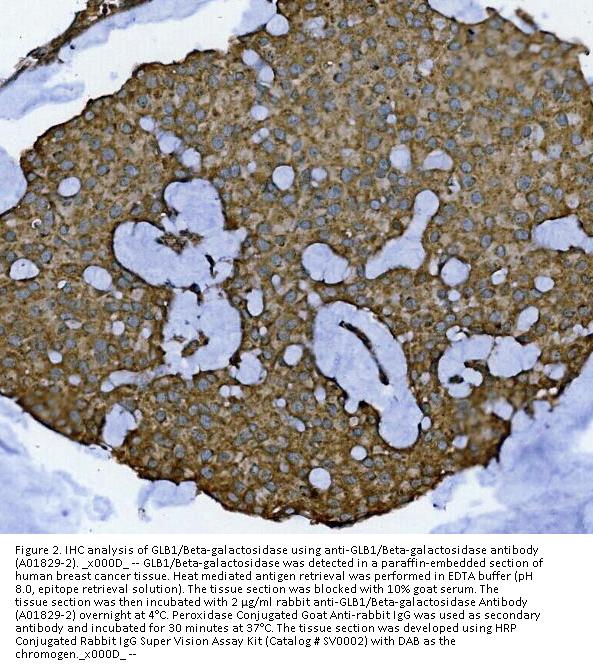

Immunohistochemistry (Paraffin-embedded Section), 2-5μg/ml, Human

Boster Bio Anti-GLB1/Beta-galactosidase Antibody Picoband® catalog # A01829-2. Tested in ELISA, Flow Cytometry, IF, IHC, ICC, WB applications. This antibody reacts with Human. The brand Picoband indicates this is a premium antibody that guarantees superior quality, high affinity, and strong signals with minimal background in Western blot applications. Only our best-performing antibodies are designated as Picoband, ensuring unmatched performance.